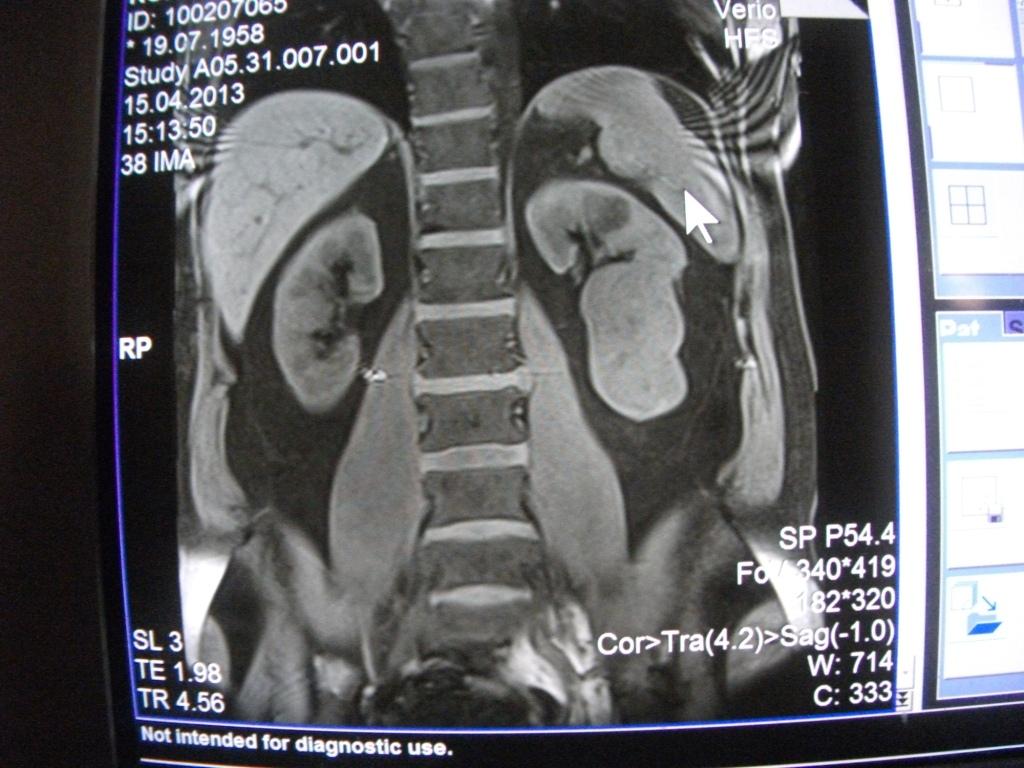

такое заключение: Левая почка: расположена обычно, увеличена, общими размерами около 13х5,5см. В области средней и нижней трети почки определяется объёмное образование неправильной формы, деформирующее наружный контур почки, распространяющиеся с чашечно-лоханочную систему. Опухоль имеет четкие неровные бугристые контуры с наличием псевдокапсулы, неоднородной структуры с признаками распада, максимальными размерами около 78,7х47х48мм